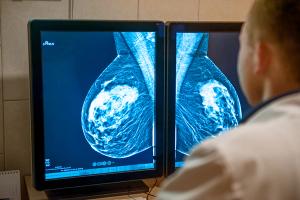

Warning systems designed to streamline interpretation of screening mammograms may not benefit interpreting radiologists or patients, a new study suggests.

Investigators at Massachusetts General Hospital proposed an algorithm for appropriate axillary nodal imaging to better align with changes in treatment algorithms for axillary nodal disease in patients with breast cancer.

Feminizing hormone therapy may increase the risk of breast cancer in transgender women, a growing body of research suggests, underscoring a need for health care providers to understand the risks, breast imaging features, and health care needs of this demographic.

A nuanced approach is needed to weigh the risk of vaccination-associated axillary lymphadenopathy against the risk of delaying breast cancer screening.